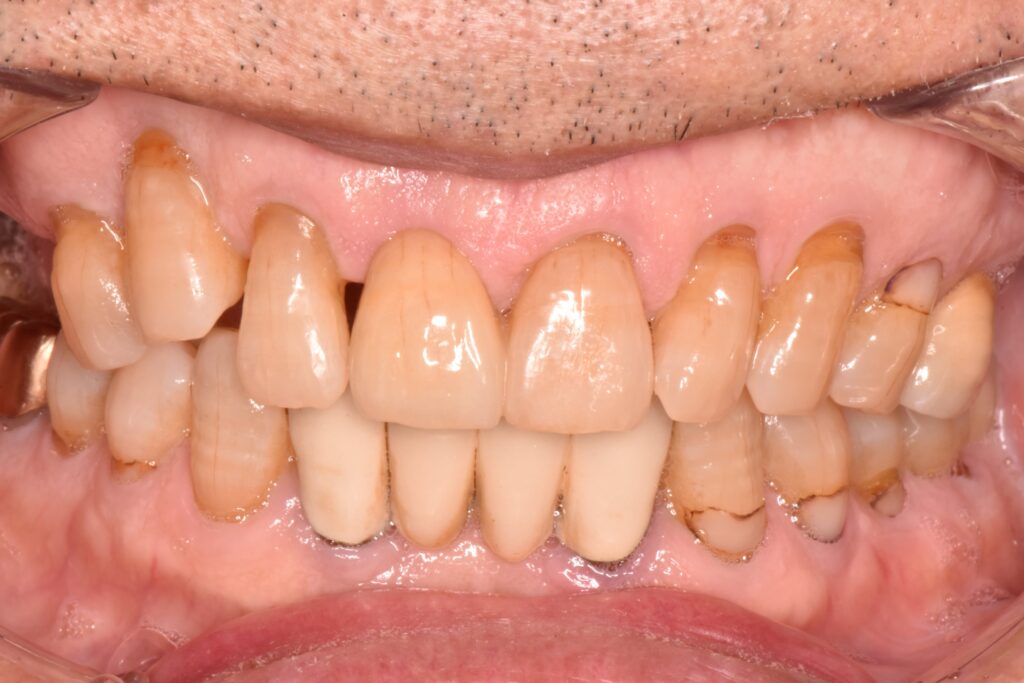

抜歯直後の口の中の写真です。

抜歯と同日に仮の歯を入れることで見た目の改善を図っています。この時は噛み合わせを全く与えていないため、隣の歯よりも短くしています。

また、抜歯を行うと残っていた周囲の骨が吸収し審美的に不利になるため、抜歯と同時に歯槽堤温存術(Alveolar ridge preservation)と呼ばる方法で、可能な限り骨が吸収しないような治療を併用しています。

この状態で歯ぐきや歯槽骨が治癒するのを待ってから最終的な歯を作製していきます。

歯ぐきが綺麗に治癒するとこのように歯ぐきが凹んだ形となります。

片方の裏側だけに支えを持たせて、接着を行いました。支えとなっている部位はほとんど削らずに治療をしています。

抜歯直後から治療を行ったことで可能な限り審美的に治療を行うことができました。